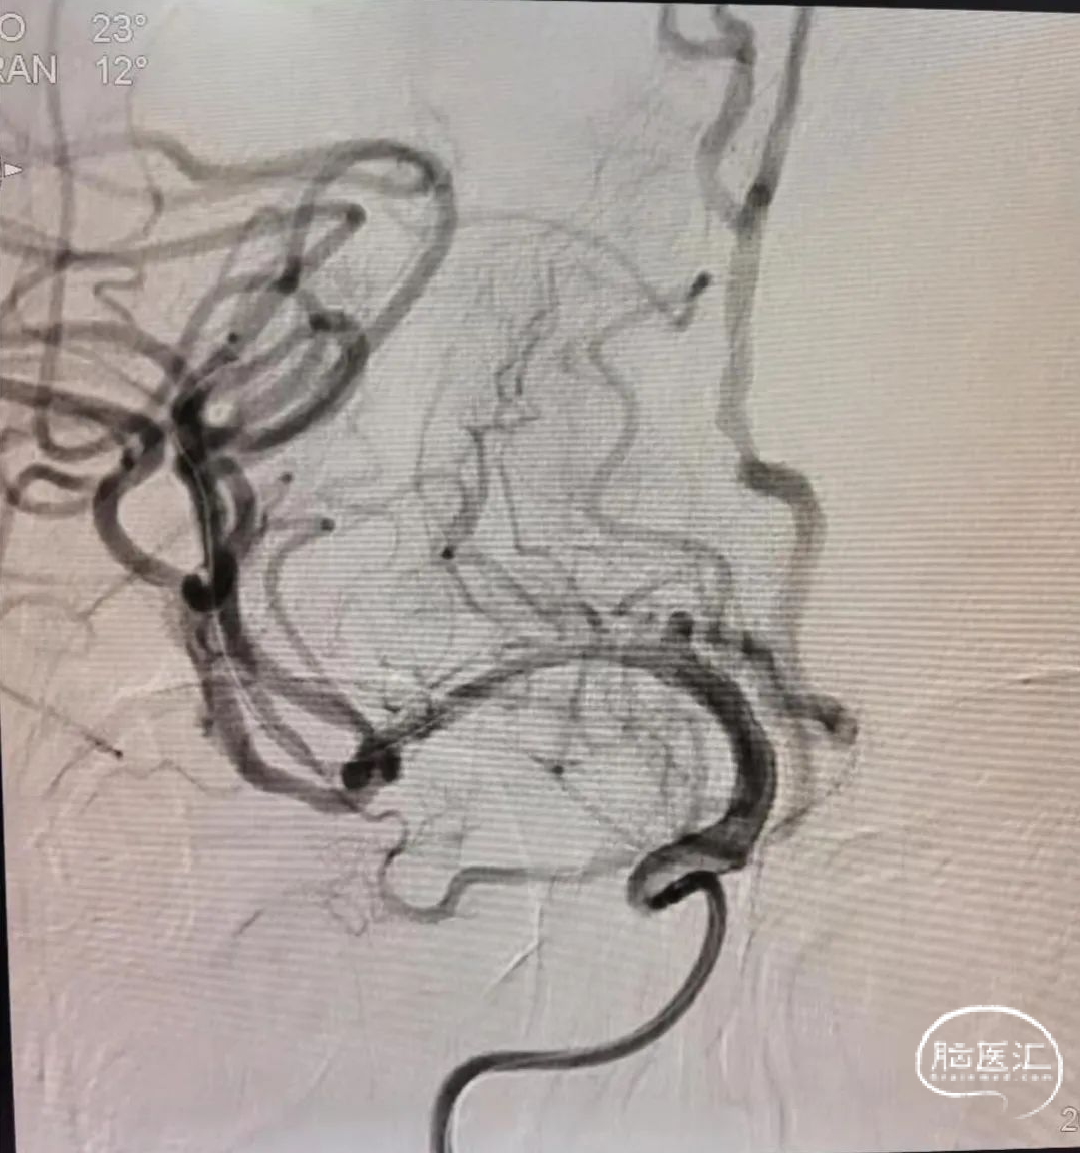

右大脑中动脉极重度狭窄球囊扩张术。

0.014 ” 2m微导丝结合微导管穿斑块通过狭窄进入上干到达M2后撤出微导管,选择2.0*15mm通桥白驹球囊,沿导丝无明显阻力顺利到达病变部位,缓慢6atm扩张一次。

撤压后球囊回抱良好,扩张后狭窄明显改善,远端血流恢复良好。等待20分钟后再次复查常规正侧位造影,发现原血管狭窄部位管径基本恢复,未见明显血管回缩,血流状态稳定,故不考虑支架植入。